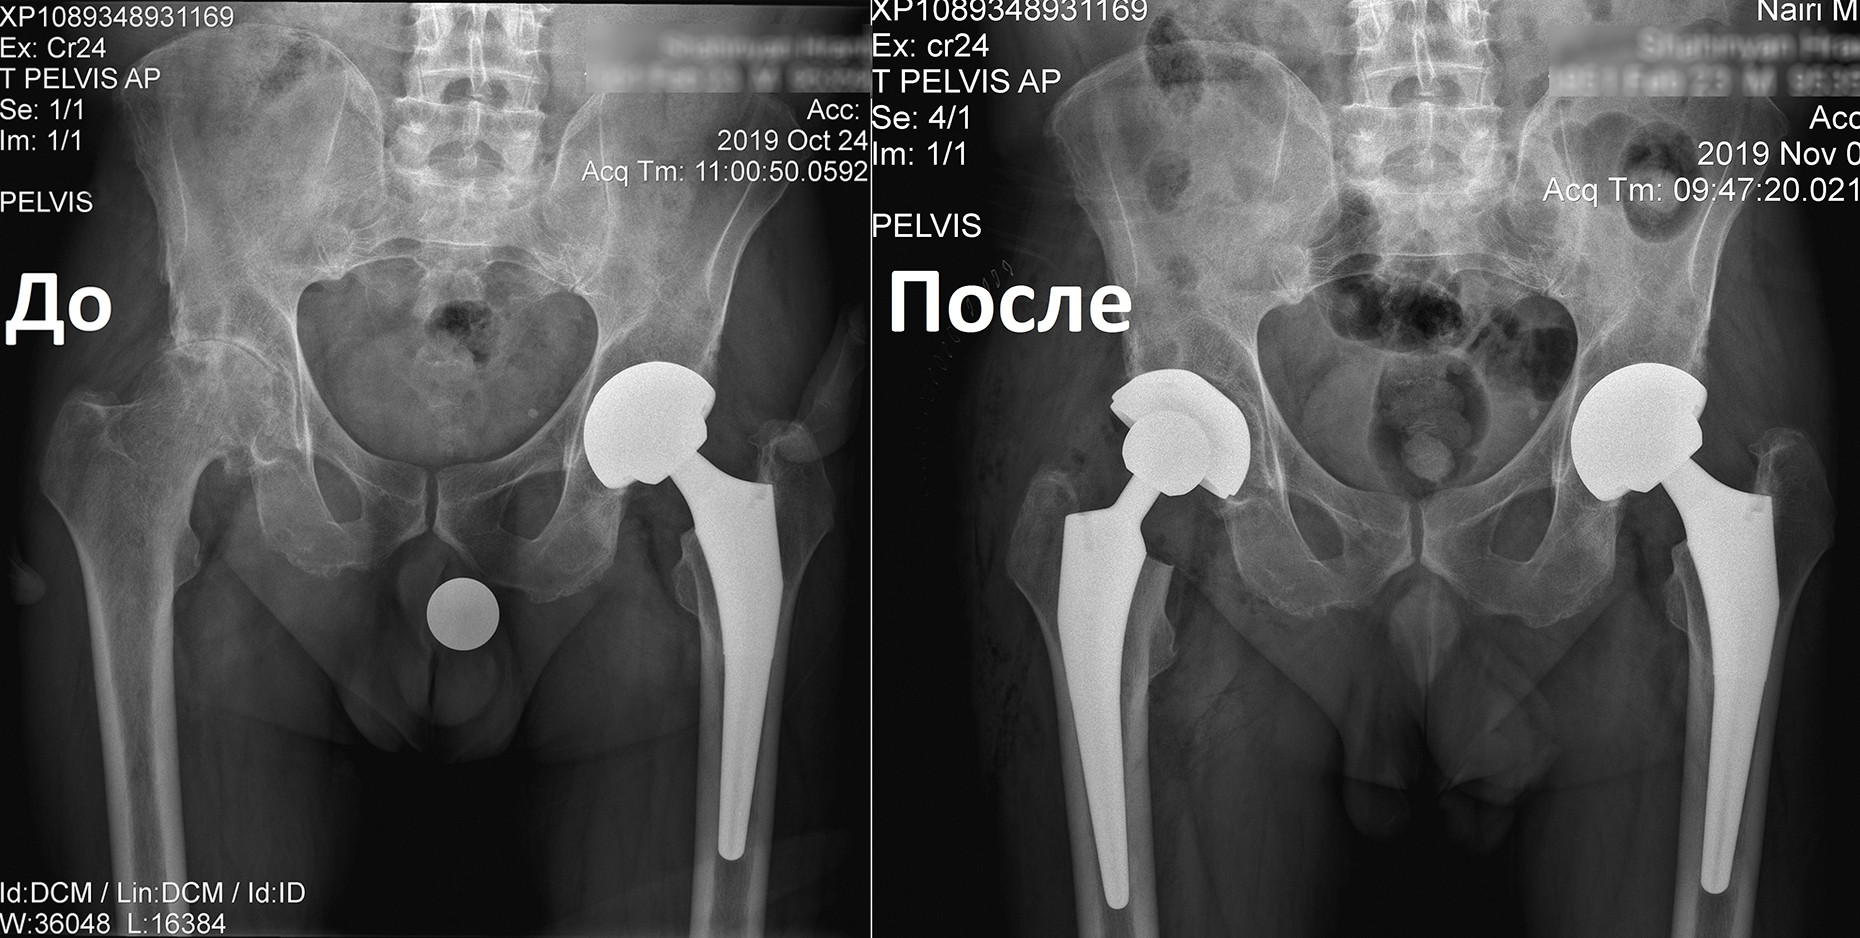

«Նաիրի» բժշկական կենտրոն էր դիմել 1951 թ. ծնված տղամարդ՝ երկկողմանի անգիլիզացնող կոքսարթրոզով, առաջին աստիճանի ճարպակալումով: Պացիենտը գանգատվում էր մշտական ցավերից, շարժումների խիստ սահմանափակումից, քայլելու դժվարությունից՝ անգամ հենակների oգնությամբ:

Որոշում կայացվեց իրականացնել փուլային երկու վիրահատություն: Առաջինը վիրահատվեց ձախ ոտքը, քանի որ այդ վերջույթում ձևախախտումն առավել արտահայտված էր:

Երկու ամիս անց, երբ պացիենտը սկսեց քայլել առանց հենակների, վիրահատվեց նաև աջ ոտքը: